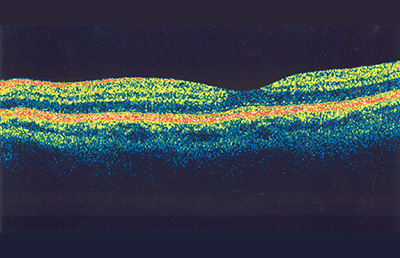

Optical Coherence Tomography (OCT) is performed as required to analyse the various structures of the eye. This test is like an ultrasound except that instead of using sound waves, it uses an infrared laser beam.

Without touching the eye, it provides images of the back of the eye (retina) as well as the front of the eye (cornea). This is the same technology used by the IOLMaster for measuring the dimensions of the eye. It provides very fine detail, down to the range of microns.

In addition to the examination by the ophthalmologist, this scan provides important information about the health of the eye as well as providing information that is important in planning cataract surgery.

Normal retina.